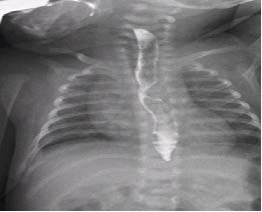

A los 23 días de vida, el recién nacido comenzó con dificultades para tragar. Con sus antecedentes, se realizó un esofagograma con contraste baritado, objetivándose una indentación lateral izquierda en esófago medio, sugerente de anomalía vascular. (Figura2).

Figura 2. Esofagograma con contraste baritado